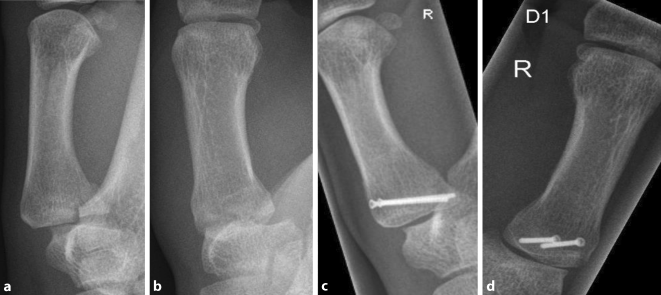

A bennett fracture is a fracture of the base of the thumb resulting from forced abduction of the first metacarpal.

Download iate, european union, 2017. Bennett fracture is a fracture of the base of the first metacarpal bone which extends into the carpometacarpal (cmc) joint. Was bedeutet der name bennett'sche fraktur? Bei sturz auf die hand. Bennett fraktur in anderen sprachen: Super versatile and can be a support or a dps. Der mittelhandknochen wird durch den zug der hier ansetzenden sehne des m. Den bennett fraktur (också bennett luxation fraktur ) är en fraktur vid basen av det första metakarpala benet som sträcker sig in i tummen sadeln fogen. New guide because a lot. From wikimedia commons, the free media repository. Fraktur komplikasi berhubungan dengan bennetts fracture adalah fraktur dislokasi sendi carpometakarpal i dengan garis patah oblik. Fracture of the base of the first metacarpal bone. Mittelhandknochens nach sturz auf den.